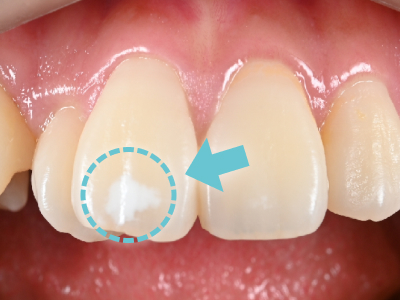

ホワイトスポットとは、歯の表面に現れる「白い斑点」のことです。

主な原因としては、初期のむし歯によるものや、歯の成長過程でエナメル質が十分に形成されなかった「エナメル質形成不全」などが挙げられます。

痛みはありませんが、前歯など目立つ場所にできることが多く、見た目のお悩みにつながりやすい症状です。